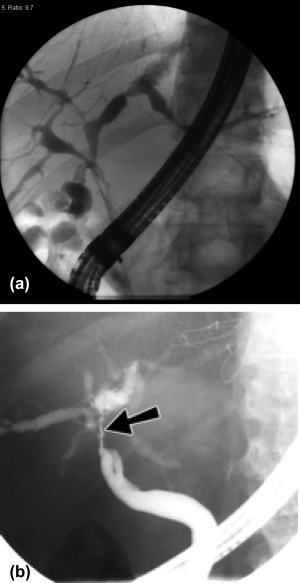

Figure 2.

(A) Multiple biliary NASs. (B) Biliary NASs. Single non‐anastomotic biliary stricture.